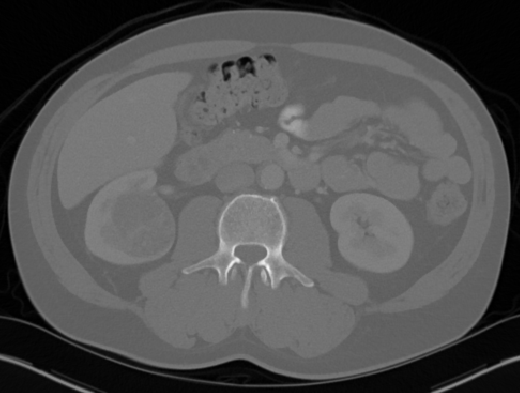

Edge-Aware 3D Image Segmentation Networks

[91]: Automated segmentation of kidneys and kidney tumors is an important step in quantifying the tumor’s morphometrical details to monitor the progression of the disease and accurately compare decisions regarding the kidney tumor treatment. Manual delineation techniques are often tedious, error-prone and require expert knowledge for creating unambiguous representation of kidneys and kidney tumors segmentation. We propose a 3D end-to-end edge-aware FCN for reliable kidney and kidney tumor semantic segmentation from arterial phase abdominal 3D CT scans. Our segmentation network consists of an encoder-decoder architecture that specifically accounts for organ and tumor semantics. We evaluate our model on the 2019 MICCAI KiTS Kidney Tumor Segmentation Challenge dataset. -

Kidney and Kidney Tumor Segmentation

Kidney cancer accounted for nearly 175,000 deaths worldwide in 2018 [13], and it is projected that 14,770 deaths will occur due to the disease in 2019 in the US [111]. Current kidney tumor treatment planning includes Radical Nephrectomy (RN) and Partial Nephrectomy (PN). In RN, both the tumor and the affected kidney are removed whereas in PN the tumor is removed but kidneys are saved [116]. Although RNs were historically prevalent as a standard treatment procedure for kidney tumors, new capabilities for earlier detection of the tumors as well as advancements in surgery has made PNs a viable treatment approach [53].

Traditionally, various techniques such as deformable models [86], GrabCuts, region growing and atlas-based methods have been applied to the problem of kidney segmentation. In recent years, researchers have attempted to leverage the power of deep learning and CNNs to build segmentation frameworks that are more automated and less dependant on incorporation of prior shape statistics. Thong et al. [119] proposed a 2D patch-based approach for kidney segmentation in contrast-enhanced CT scans by leveraging a modified ConvNet.

Jackson et al. [62] developed a framework for detection and segmentation and of kidneys in non-contrast CT images by utilizing a 3D U-Net. Yang et al. [128] proposed a method for kidney and renal tumor segmentation in CT angiography images by a modified residual FCN that is equipped with a pyramid pooling module. Furthermore, Yin et al. [130] employed a cascaded approach for segmentation of kidneys with renal cell carcinoma by training a CNN that predicts a bounding box around the kidney and a subsequent CNN that segments the kidneys. Recently, Xia et al. [126] proposed a two-stage approach for the segmentation of kidney and space-occupying lesion areas by using SCNN and ResNet for image retrieval and SIFT-flow and MRF for smoothing and pixel matching.